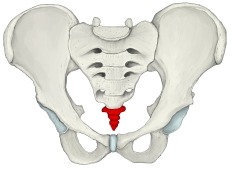

尾 骨 ( びこつ、英:coccyx )

・全体としては逆三角形の形を呈する。

・第1尾椎にあたる部分の下から第1尾椎神経が出るが、それ以下からは神経は出ない。 ・仙骨と骨化(ossification)しない場合は、椎間円板を介して関節する。(仙尾関節)